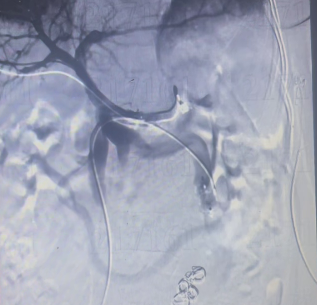

明确诊断后,介入医学科团队决定用微创介入手术帮王阿姨解决问题。手术在局部麻醉下进行,医生先穿刺股静脉做左肾静脉造影,没找到明确的畸形血管;又改行经皮肝穿刺门静脉,顺着脾静脉、肠系膜上静脉造影,终于看清了那团迂曲扩张的畸形血管团。

随后,医生把细导管精准插进畸形血管里,依次释放血管塞和弹簧圈,稳稳封堵住了分流的通道。整个手术微创完成,王阿姨全程清醒,没受多少罪。